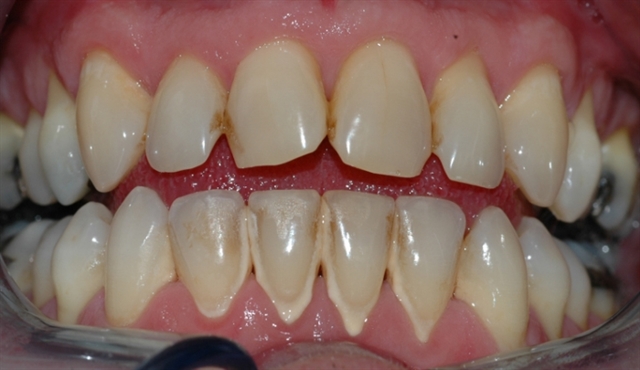

Bildet viser et tannsett med synlig tannsten og misfarging.

• perio stor 6